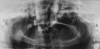

The following case report shows the systematic application of the above-mentioned principles. A 5-year-old male who had received a diagnosis of hereditary hypohidrotic ED was presented by his mother, who stated that she wanted his teeth to appear normal for school (Figure 1 and Figure 2). On clinical and radiographic examinations, it was noted that the patient had anodontia in the mandible, only two erupted primary incisors in the maxilla, and three developing tooth buds in the maxillary anterior region. Alveolar bone was significantly deficient (Figure 3). The erupted maxillary incisors had the characteristic cone shape (Figure 4). The patient presented with a knife-edge shaped mandibular residual ridge and significant xerostomia (Figure 5). After evaluating the patient’s financial, social, and oral status, the authors developed a treatment plan that involved fabrication of maxillary and mandibular complete dentures. It was decided to perform endodontic therapy on the two maxillary incisors and reduce them to the gingival level for their use as overdenture abutments. The root canals were filled with silver amalgam up to 3 mm inside the canal space (Figure 6).

Figure 3  Pretreatment panoramic radiograph displaying the oligodontia and lack of alveolar bone development.

Figure 3